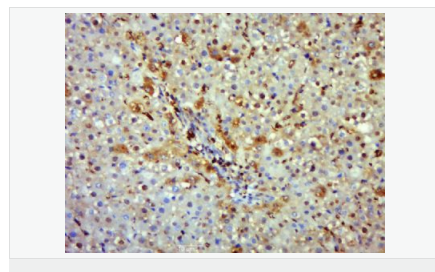

| 產品應用 | WB=1:500-2000 IHC-P=1:100-500 IHC-F=1:100-500 Flow-Cyt=1μg/Test ICC=1:100-500 IF=1:100-500 (石蠟切片需做抗原修復) not yet tested in other applications. optimal dilutions/concentrations should be determined by the end user. |

| 產品介紹 | Nitric oxide (NO) is an inorganic, gaseous free radical that carries a variety of messages between cells. Vasorelaxation, neurotransmission and cytotoxicity can all be potentiated through cellular response to NO. NO production is mediated by members of the nitric oxide synthase (NOS) family. NOS catalyzes the oxidization of L-arginine to produce L-citrulline and NO. Two constitutive isoforms, brain or neuronal NOS (b or nNOS, type I) & endothelial cell NOS (eNOS, type III), and one inducible isoform (iNOS, type II), have been cloned. All NOS isoforms contain calmodulin, nicotinamide adenine dinucleotide phosphate (NADPH), flavin adenine dinucleotide (FAD), and flavin mononucleotide (FMN) binding domains. Nitric oxide synthase is expressed in liver, macrophages, hepatocytes, synoviocytes, stimulated glial cells and smooth muscle cells. Cytokines such as interferon-gamma (IFN), tumor necrosis factor (TNF), interleukin-1 and -2, and lipopolysaccarides (LPS) cause an increase in iNOS mRNA, protein, and activity levels. Protein kinase C-stimulating agents exhibit the same effect on iNOS activity. After cytokine induction, iNOS exhibits a delayed activity response which is then followed by a significant increase in NO production over a long period of time. Human iNOS is regulated by calcium/calmodulin (in contrast with mouse NOS2). Function: Produces nitric oxide (NO) which is a messenger molecule with diverse functions throughout the body. In macrophages, NO mediates tumoricidal and bactericidal actions. Also has nitrosylase activity and mediates cysteine S-nitrosylation of cytoplasmic target proteins such COX2. Subunit: Homodimer. Binds SLC9A3R1. Tissue Specificity: Expressed in the liver, retina, bone cells and airway epithelial cells of the lung. Not expressed in the platelets. Similarity: Belongs to the NOS family. Contains 1 FAD-binding FR-type domain. Contains 1 flavodoxin-like domain. SWISS: P35228 Gene ID: 4843 Database links: Entrez Gene: 4843 Human Entrez Gene: 18126 Mouse Omim: 163730 Human SwissProt: P35228 Human SwissProt: P29477 Mouse Unigene: 709191 Human Unigene: 2893 Mouse Unigene: 10400 Rat Important Note: This product as supplied is intended for research use only, not for use in human, therapeutic or diagnostic applications. 合成與降解(Synthesis and Degradation) 催化生物體內一氧化氮(NO)生成的酶。分神經型一氧化氮合成的酶(nNOS or NOS-1)、誘導型一氧化氮合成的酶(iNOS or NOS-2)、內皮型一氧化氮合成的酶(eNOS or NOS-3)。 |